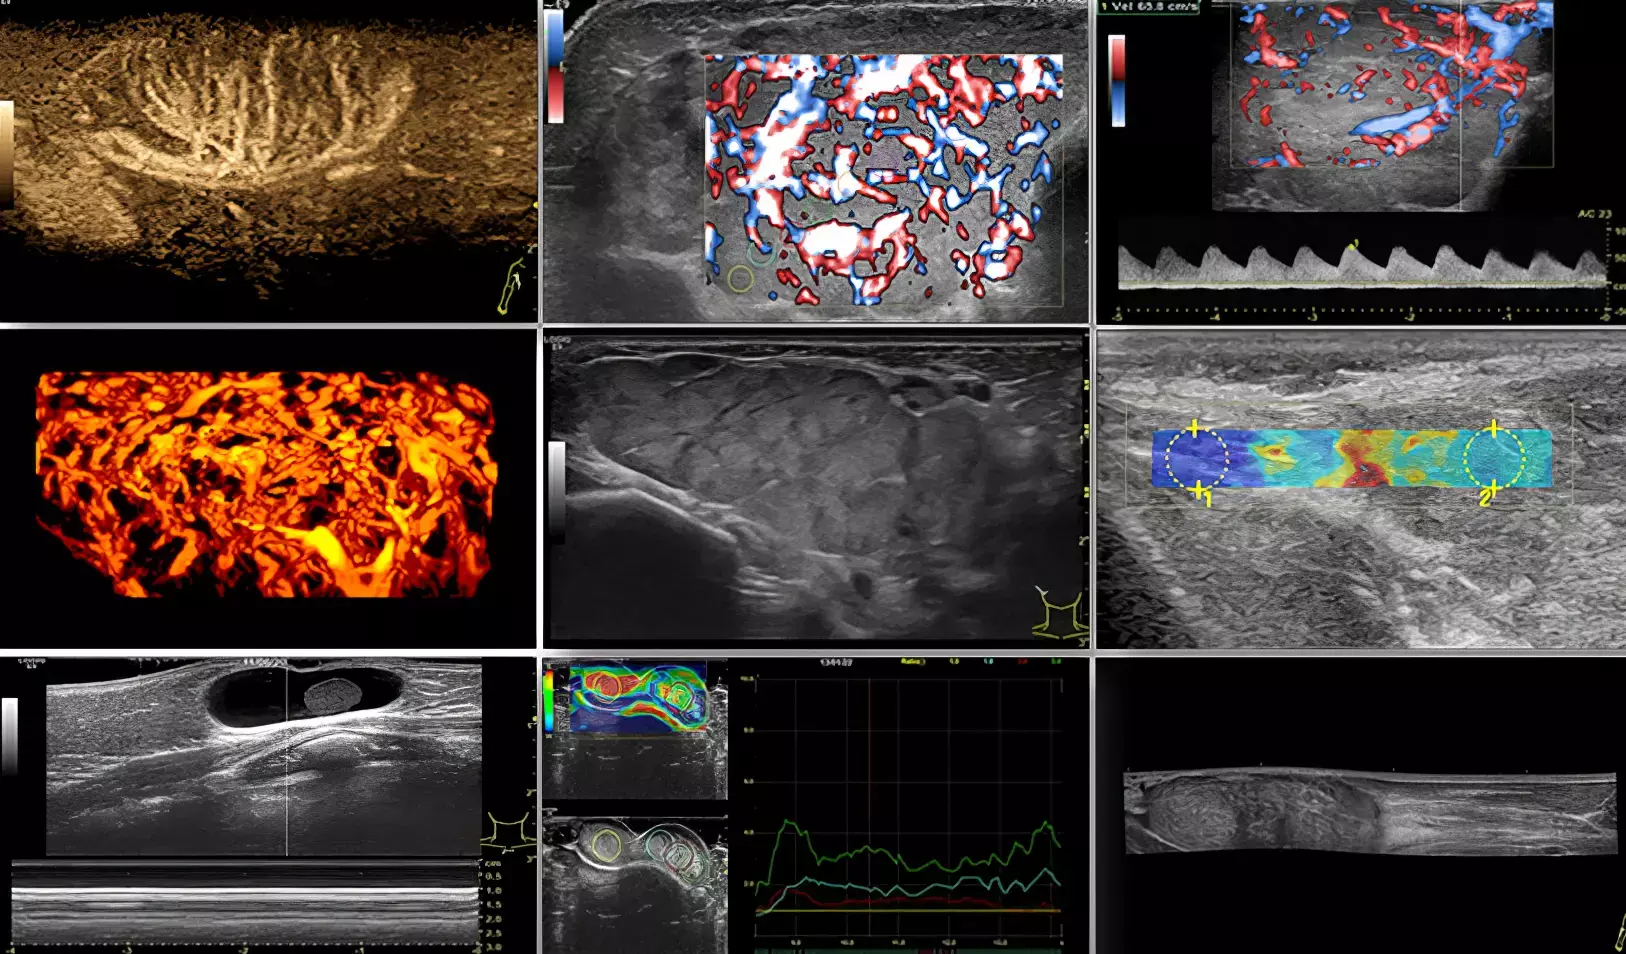

Поскольку технология CEUS пока не используется, основой мультимодального подхода в Беларуси становится комбинация высококачественного В-режима, цветового допплера и, где это возможно, эластографии (см. рис.).

Рисунок. Режимы и модальности диагностического ультразвука.

- В-режим + допплер — «золотая пара». Оценка структуры + васкуляризации. Аваскулярное образование? Скорее доброкачественное (киста, гематома). Гиперваскулярное солидное или кистозно-солидное с хаотичными сосудами образование? Требует исключения опухоли.

- Эластография — виртуальная пальпация. Особенно ценна для диагностики новообразований в поверхностно расположенных органах и тканях (лимфатические узлы, щитовидная и молочные железы, тестикулы, мягкие ткани). Повышенная жесткость (в абсолютных или индексированных показателях) — серьезный аргумент в пользу злокачественности и показаний к биопсии.

Важно: для корректного использования нужны внутрибольничные или локальные референсные значения эластографических показателей. Некоторые доброкачественные процессы (с кальцинациями, фиброзированием) также могут давать жесткую картину, поэтому интерпретация всегда должна быть в клиническом контексте.